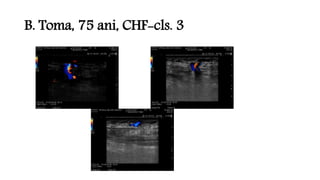

B. Toma, 75 ani, CHF-cls. 3

B. Toma, 75ani, CHF-cls. 3